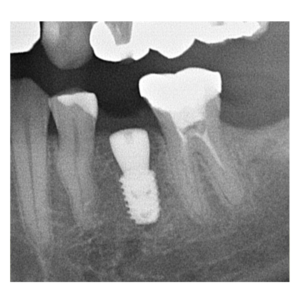

治療途中のインプラント症例

治療途中のインプラント症例です。

歯がグラグラして揺れる |

52歳 男性 |

1時間 |

治療費(インプラント手術費) |

¥350,000(税別) |

腫れ・痛み・神経損傷・インプラント周囲炎・骨吸収 など |